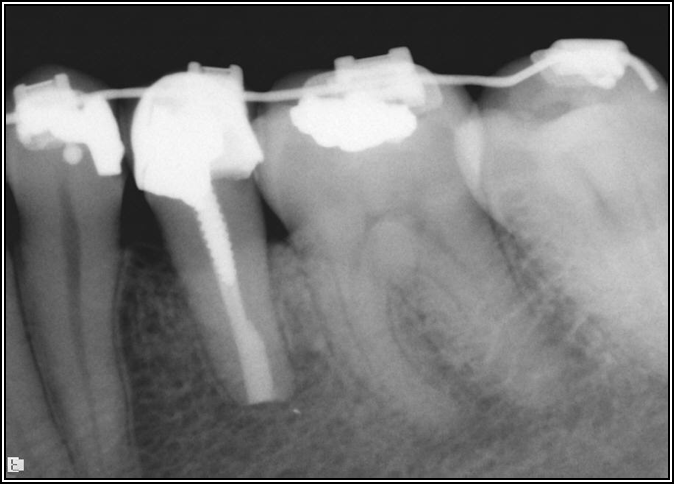

Fig 8. Bitewing revealed decay and other problems.

Figure 8

With the bitewing shown in Figure 8, it became clear there was gross decay in tooth No. 3 that could not be seen on the PA, and there was a periodontal defect, a pulp stone, in No. 2. There was also a class V lesion revealing the bruxism, flat occlusion, multiple restorations in No. 30, a post in No. 31, and decay on No. 2 as well. The post in No. 31 was useless because when a post is placed, it must be the right length, width, and size. If the post is too short, there will be a greater fulcrum and the tooth will break. If it is too long, the clinician can break it by wedging it. If it is too short, it will not hurt the tooth, but it will not provide any valuable function. It is overall preferable to do posts in teeth having just single restorations rather than abutments for bridges because those teeth are already under greater force. If the technique is not performed correctly, iatrogenic issues may result.